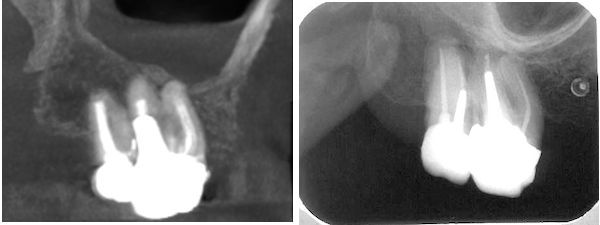

33-jährige Patientin (18.08.1981 / 404)

Bei der Wurzelbehandlung hat eine Nervnadel die Kieferhöhle eröffnet. Auf dem Röntgenbild verdeckt die Kortikalis der Kieferhöhlenwand die Wurzelspitze. Sie befindet sich etwa beim roten Pfeil.

33-jährige Patientin (22.02.1982 / 404)

Bei der Wurzelfüllung ist etwas Wurzelfüllmaterial (AH26)über die Wurzelspitze hinausgepresst worden. Das AH26 ist weitgehend keimfrei, liegt auf der Schleimhaut, härtet in 24 h aus und ist ein kleiner Fremdkörper in der Kieferhöhle.